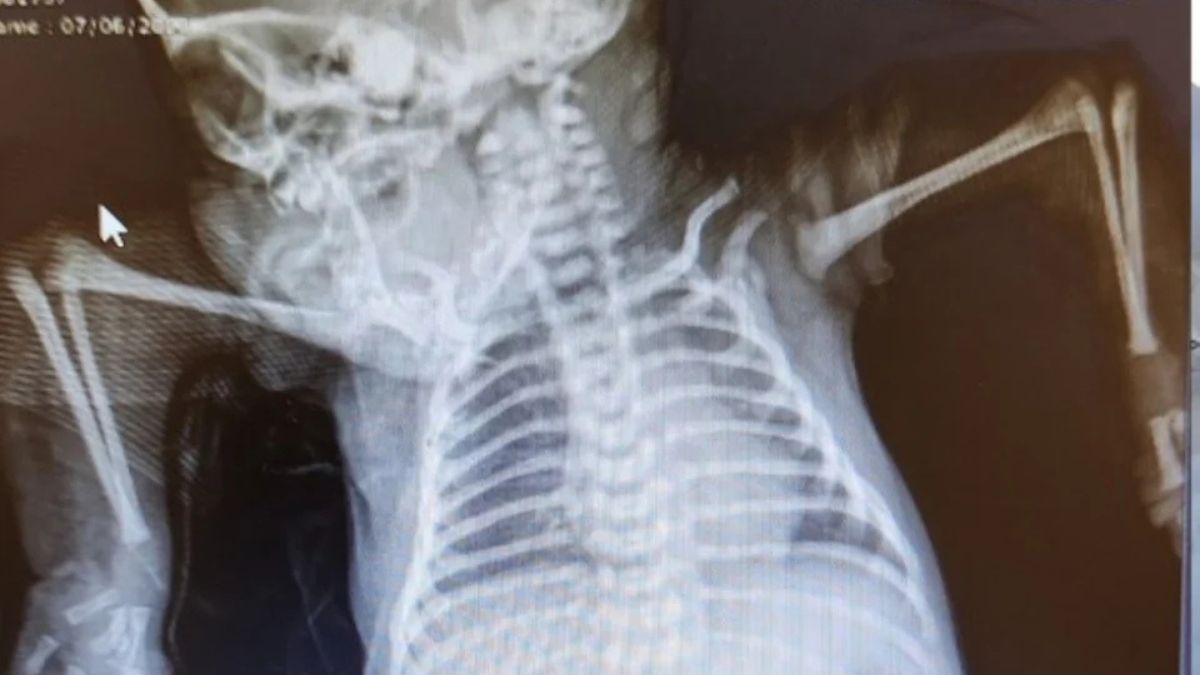

Αποτέλεσμα της πάθησης αυτής ήταν το μωρό να γεννηθεί με τους ώμους του στραμμένους προς τα κάτω και τους αγκώνες του προς τα πάνω. Οι αρθρώσεις του ήταν σκληρές και κοντές, με αποτέλεσμα να μην μπορεί να κινήσει τα χέρια ή τα δάχτυλά του.

Η Maria da Conceição Soares, εργοθεραπεύτρια που ήταν υπεύθυνη για την περίπτωση του João Pedro, σοκαρίστηκε όταν τον είδε. «Είχε περάσει από όλο το νοσοκομείο και κανείς δεν είχε δει ποτέ κάτι τέτοιο. Η θέση στην οποία γεννήθηκε είναι πολύ σπάνια», εξηγεί.

Σύμφωνα με την ίδια, δεν υπάρχει συγκεκριμένο πρωτόκολλο για τη θεραπεία περιπτώσεων αρθρογρύπωσης όπως αυτή. Έπρεπε να αναλύσει την περίπτωση για να καταλήξει σε μια στρατηγική, να διορθώσει τη δυσμορφία και να επαναφέρει τα χέρια στη σωστή τους θέση.